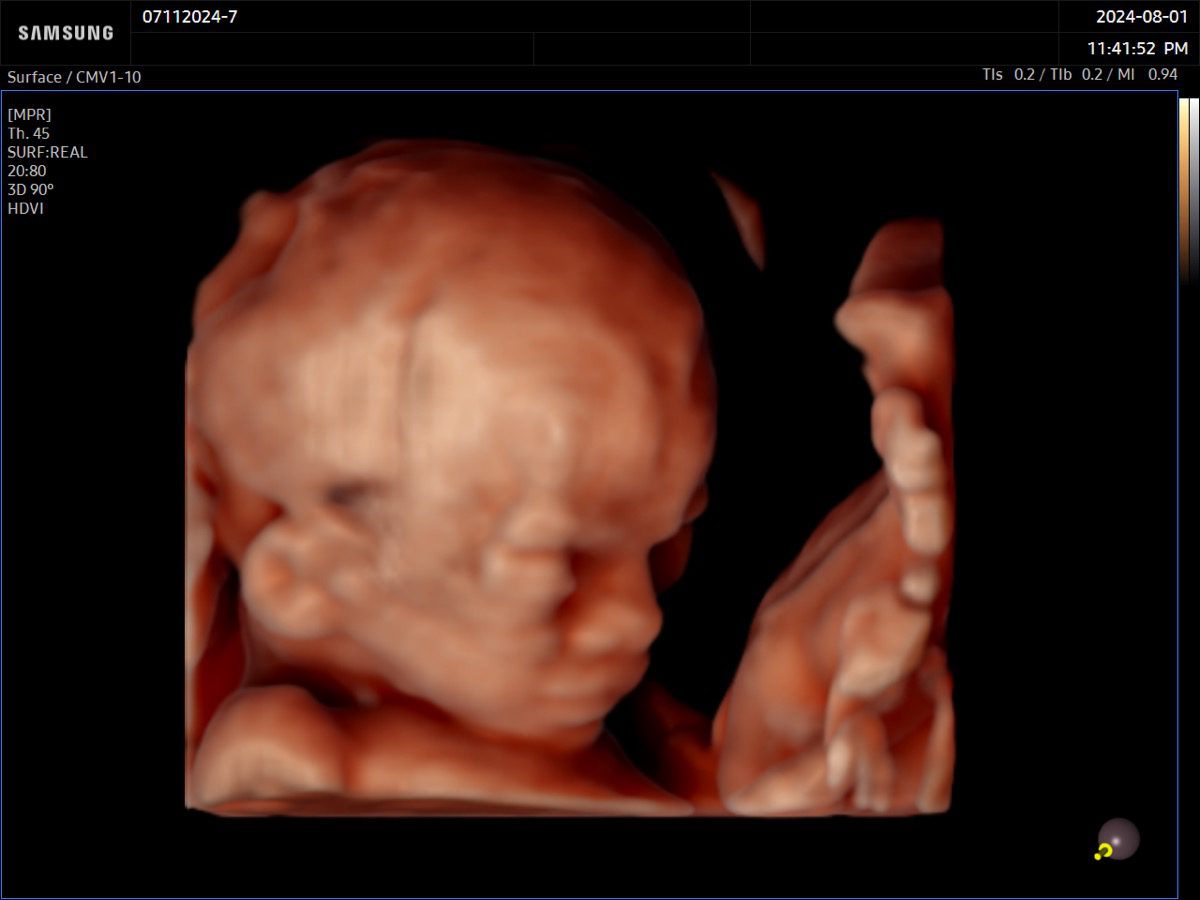

Comprehensive, advanced and expert MFM care for high-risk pregnancies

- Fetal anomalies